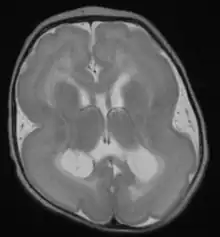

| Lissencephalic brain of a human, lacking surface convolutions (Gyrification) | |

Lissencephaly (meaning "smooth brain")[1] is a set of rare brain disorders where the whole or parts of the surface of the brain appear smooth.[2] It is caused by defective neuronal migration during the 12th to 24th weeks of gestation resulting in a lack of development of brain folds (gyri) and grooves (sulci).[3] It is a form of cephalic disorder. Terms such as agyria (no gyri) and pachygyria (broad gyri) are used to describe the appearance of the surface of the brain.